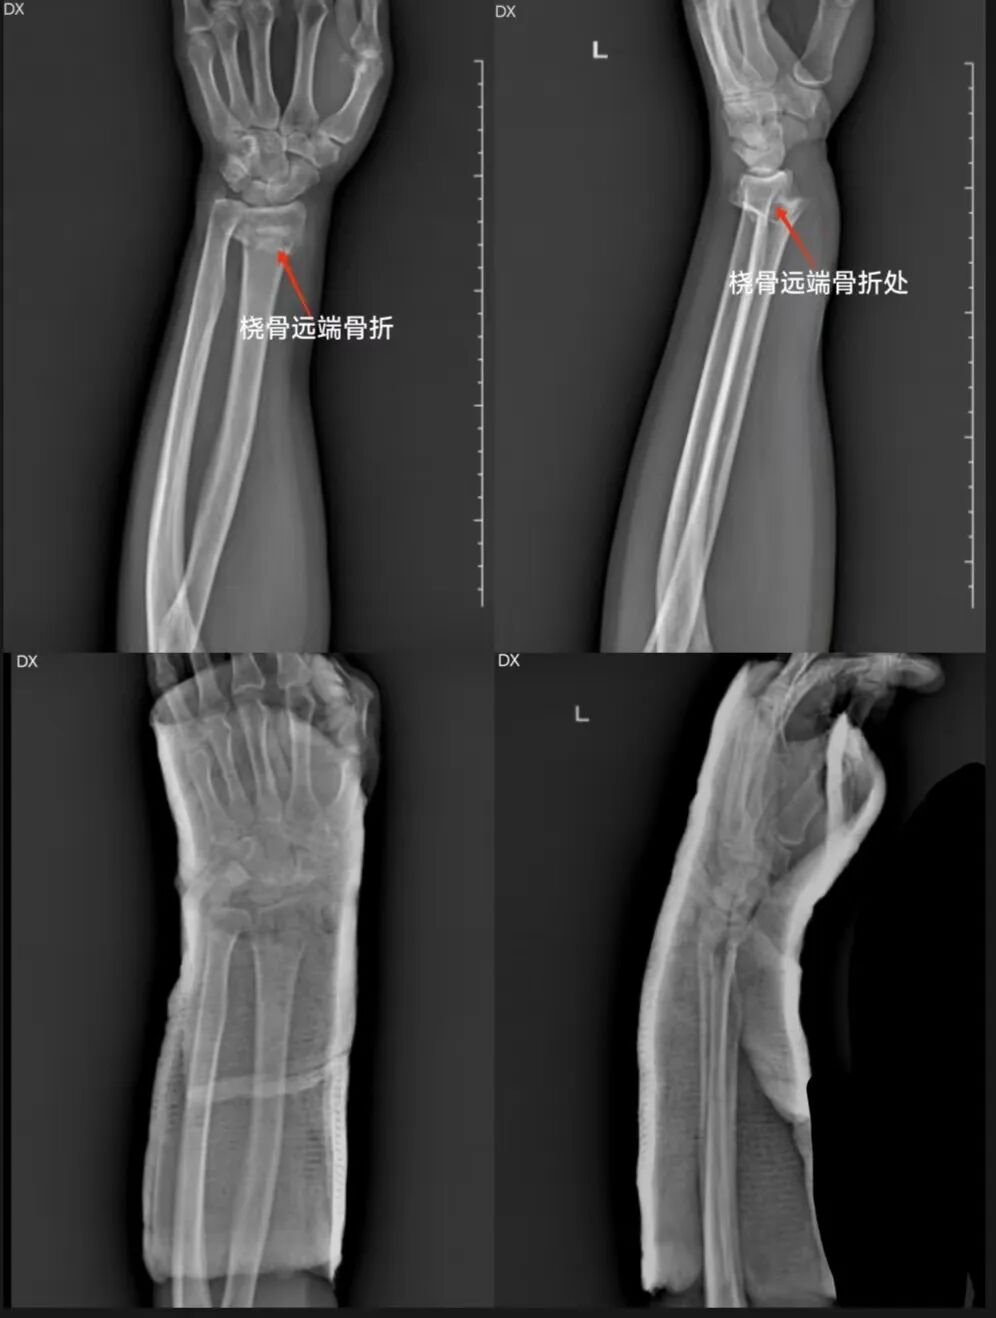

辅助检查:X线

初步诊断:桡骨远端骨折